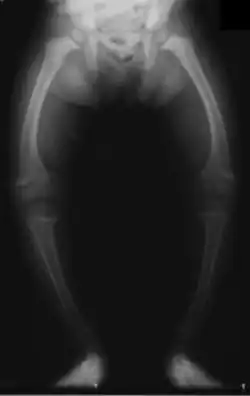

| X-ray of a two-year-old with rickets, demonstrating a marked bowing of the femurs and decreased bone density | |

An X-ray or radiograph of an advanced patient with rickets tends to present in a classic way: the bowed legs (outward curve of long bones of the legs) and a deformed chest. Changes in the skull also occur, causing a distinctive "square-headed" appearance known as "caput quadratum".[18] These deformities persist into adult life if not treated. Long-term consequences include permanent curvatures or disfiguration of the long bones, and a curved back.[19]